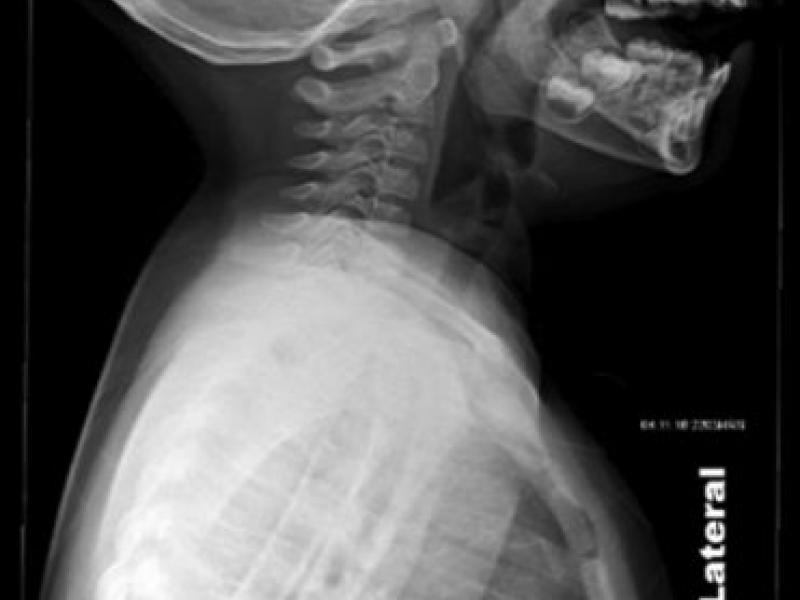

Imaging Case: 8 Year Old Girl with Shortness of Breath

Case: An 8 year old girl presents to the Emergency